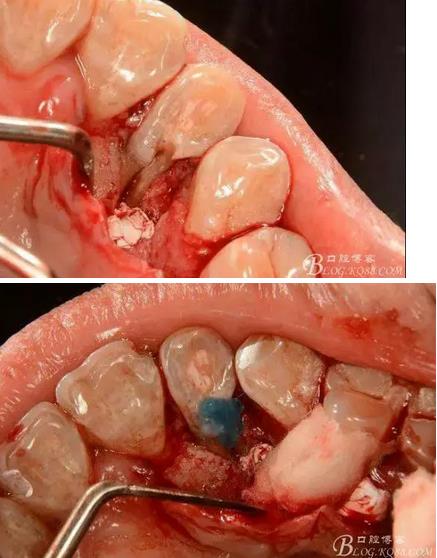

(3) 處理:常規(guī)開髓,修整髓腔,15#k銼探查根管,根管測量儀確定工作長度,根長22mm,大錐度手動銼完成根管預備,沒換一次銼沖洗根管一次,消毒,干燥根管,暫封維他派克斯。4%阿替卡因腎上腺素行11至14局部浸潤麻醉、消毒、鋪巾,做11-14腭側(cè)牙齦水平切口并翻瓣暴露12腭側(cè)骨缺損區(qū),清理肉芽組織及壞死骨組織,清潔術區(qū),磨除根面溝,制備固位溝槽,酸蝕,粘接,光固化樹脂修復根面缺損區(qū),阻斷牙周感染途徑。拋光樹脂,沖洗創(chuàng)面,復位齦瓣,局部敷料壓迫一分鐘,對位縫合齦瓣。術后抗炎治療,7d線。